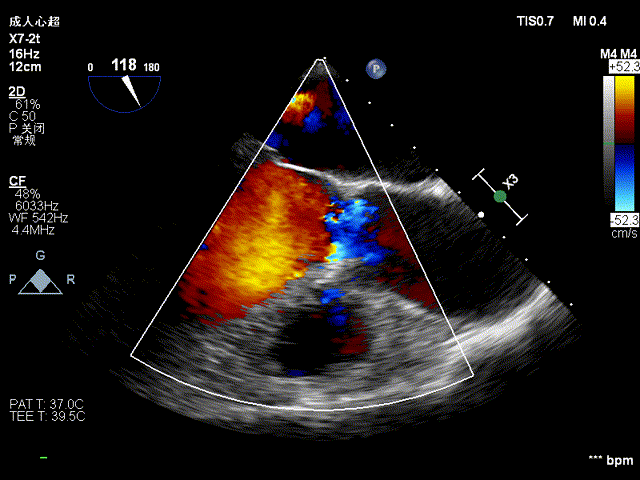

超声显示:升主动脉34mm、窦部34mm,左房(前后/横径) 41/40mm,左室(舒张期/收缩期)58/37 mm,EF 66%。彩色多普勒显示主动脉瓣和二尖瓣反流。

超声提示:左心增大;心脏瓣膜病,主动脉瓣中重度关闭不全,二尖瓣中度关闭不全。

术前超声见主动脉瓣反流:

二尖瓣中大量反流: